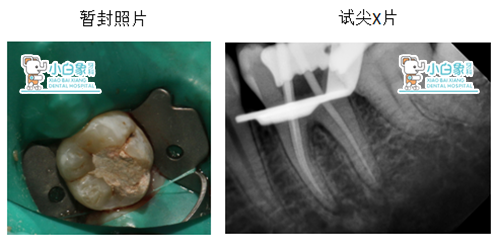

初诊时间:17.12.03 结束时间:17.12.09

X线:36合面低密度暗影近髓角

治疗前图片:

治疗:12月3日第一次治疗行36必兰麻醉下开髓揭顶,封慢失。12月9日复诊,橡皮障下预备根管三根,根长均为19mm,次氯酸钠冲洗液荡洗根管,隔湿干燥,根管内置根充糊剂+牙胶尖,磷酸锌垫底,3MZ250充填。